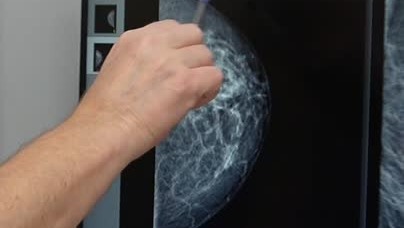

Рак молочной железы

Рак молочной железы лидирует среди причин смерти от заболеваний у женщин. Причина такой печальной ситуации в том, что часто его выявляют на последней стадии, когда метастазы уже распространились в другие органы. Чтобы избежать этого и вовремя начать лечение, нужно знать основные симптомы рака и составить свой план действий. Причины рака молочной железы Рак груди чаще всего возникает у женщин в период приближения климакса и связан с гормональными изменениями. Но в последние годы его все чаще диагностируют в молодости...

Рак молочной железы. Причины и симптомы болезни.

Рак молочной железы — очень распространенная патология, на долю которой приходится 21% всех случаев рака среди женщин. В 100 раз реже патология затрагивает мужчин. При своевременном выявлении рак молочной железы хорошо поддается лечению традиционными методами. Что такое рак молочной железы В нозологическую категорию “рак молочной железы” входит более 20 видов новообразований. Злокачественные опухоли могут быть: Патологические новообразования формируются внутри протоков, в долях органа. Причины заболевания Молочная железа — орган, очень чувствительный к эмоциональному состоянию женщины...